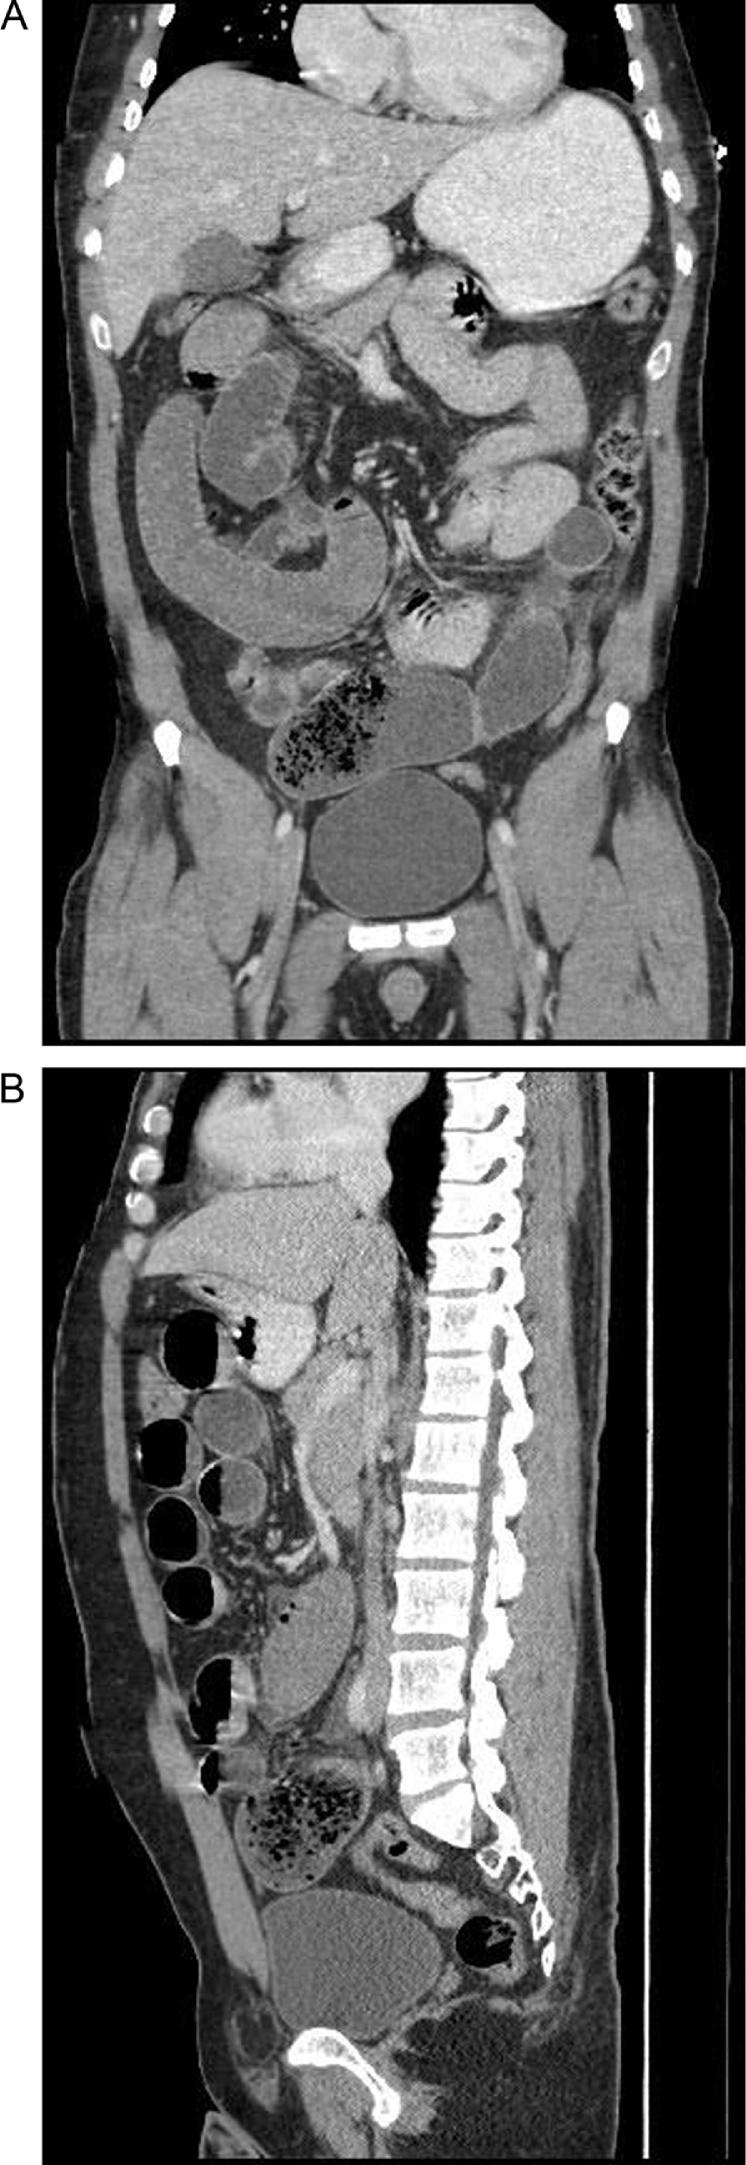

A forty-seven-year old male presented to the emergency department with a one-day history of abdominal pain associated with vomiting and constipation. Physical examination diagnostic tests revealed features of intestinal obstruction.

一名47岁男性因腹痛伴呕吐和便秘一天就诊于急诊科。体格检查和诊断性检查显示肠梗阻的特征。